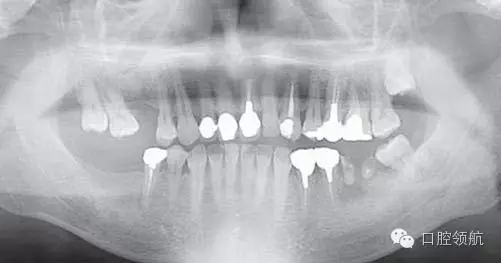

對患者進行詳細說明后,拔除后等待骨愈合6個月,再度植入手術(shù)。第二次植入時,注意了沖水充分,根據(jù)骨的狀態(tài),在缺損部中央植入。植入后2個月,按常規(guī)戴入上部結(jié)構(gòu),約6個月后,曲面斷層影像和口內(nèi)均未見異常,愈合良好(圖9)。

圖9 再植入后6個月的曲面斷層影像。